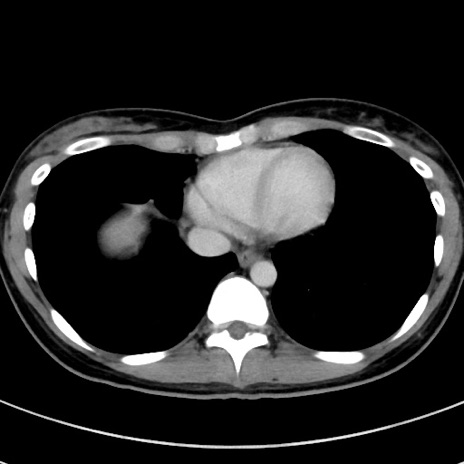

症例17(横断像)

冠状断像

【症例】20歳代女性

【主訴】嘔吐、下腹部痛

【現病歴】昨日夕食後に嘔吐し下腹部痛が出現。本日になっても嘔吐持続し改善しないため来院。

【身体所見】意識清明、BT 37.2℃、BP 108/67mmHg、腹部:平坦、やや硬、下腹部正中から右にかけて圧痛あり、反跳痛軽度あり、tapping pain(+)。

【データ】WBC 13600、CRP 14.94